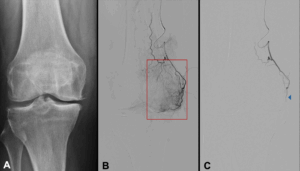

Figure 1: A) X-ray image of a 62-year-old patient with predominantly medial knee osteoarthritis (Kellgren–Lawrence grade 3). B) Pre-interventional angiogram showing pronounced hyperperfusion in the pain-correlated area supplied by the descending genicular artery; the patient’s characteristic pain was reproduced during intra-arterial contrast injection. C) Post-interventional DSA: Following embolization of the synovial hyperperfusion using temporarily resorbable microspheres, complete resolution of the hyperaemia is observed. Blue arrow: Successful, temporary embolization of the target vessel.